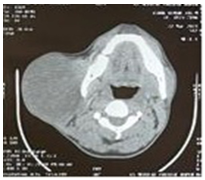

Contrast enhanced computerised tomography (CECT) shows a large mass in superficial lobe of parotid in close contact with important neurovascular structures